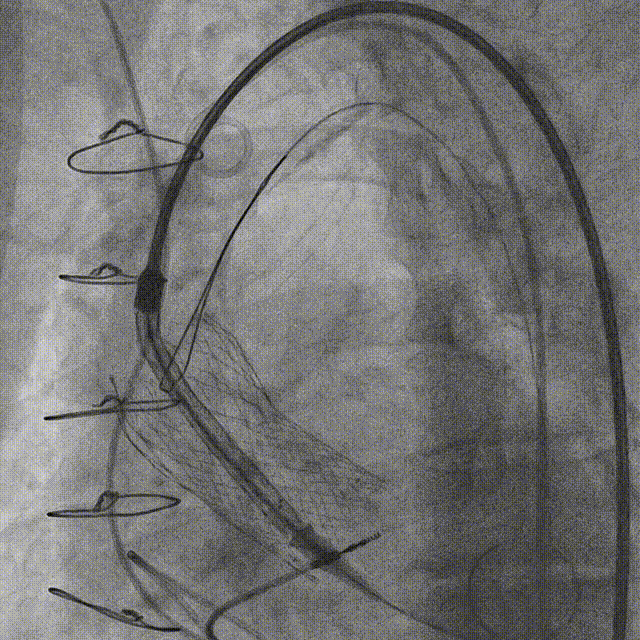

TAVR操作全过程

2.TAVR术后冠脉造影:

3.经左股动脉角度猪尾行主动脉根部造影。

4.猪尾直接跨瓣并进行左室测压。